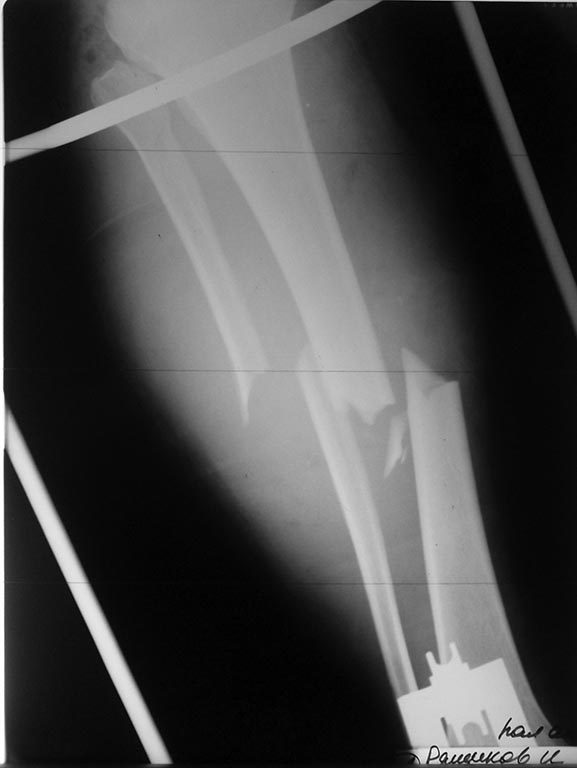

Уважаемые коллеги! Прошу поделиться опытом ведения пациентов с синдромом длительного сдавления. Пациент 27 лет поступил 16.10.17 на голень упал тяжелый предмет (с его слов сломался кран и упал), Конечность была сдавлена в течение 4 часов. При поступлении парестезии, нарушение движения, боль, отек. В с/3 голени уже сформированный участок сухого некроза. Имелись раны до 1 см - перфорация отломками. Был госпитализирован в ОРиТ. Назначена сосудистая, антибактериальная терапия. Была произведена прикорневая футлярная блокада. На следующий день пациент отметил улучшение чувствительности, увеличение объема движений в пальцах. Конечность теплая, напряженного отека нет, пульсация сосудов сохранена - положительная динамика. От фасциотомии воздержался. 17.10.17 АВФ. В последующем положительная динамика, функция почек не страдает.Хотелось бы услышать мнение о правильности тактики лечения, т.к. впервые столкнулся с данной патологией. Мнение по поводу БИОСа в первые сутки, отказ от фасциотомии у данного пациента? Сейчас имеется некроз кожных покровов на передней поверхности голени и умеренное снижение чувствительности 1 пальца. С Уважением.